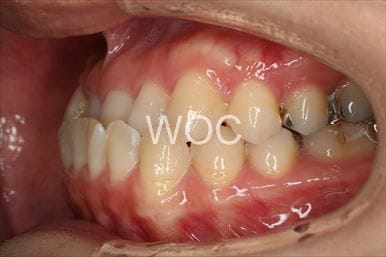

八重歯・叢生上のみ舌側矯正、下はエッジワイズ装置

上は舌側矯正を希望。ガタガタ(叢生)が強い。上顎右側中切歯・側切歯が歯科治療で連結してあったがそれを除去してから治療開始しました。

- 年齢:23歳女性

- 主訴:上下前歯のガタガタが気になる

- 基本矯正料金:103万円

- 治療期間:2年2ヶ月

- 非抜歯